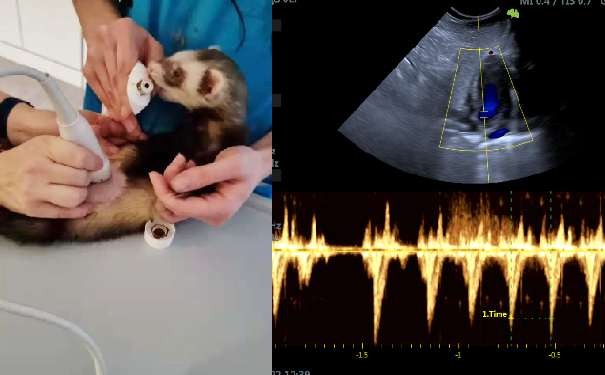

就在几周前,VINNO和德国伙伴们在柏林的一家鸟类诊所展示了一个有趣的演示,显然,由于非家养宠物 (如鸟类、外来小型哺乳动物) 的尺寸和独特特征,无法使用CT,而兽用超声波派上了大用场。

近年来超声成像的进步极大地使我们的鸟类和外来动物受益,使用在小型动物身上也能获得更快更好的成像,从而将控制和麻醉的风险降至最低。VINNO一直与全球兽医诊所、研究所和大学合作,帮助客户在研究、治疗方面做出更明智的决定。

在德国使用飞依诺兽用超声